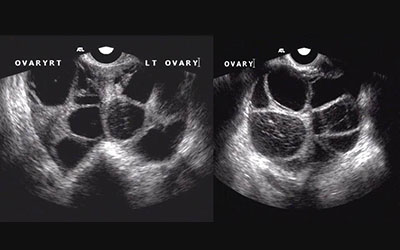

You will need an ultrasound scan of your ovaries to measure how big they are and whether there is any fluid build-up in your abdomen. Some blood test to measure how concentrated your blood is and how well your kidneys are working.